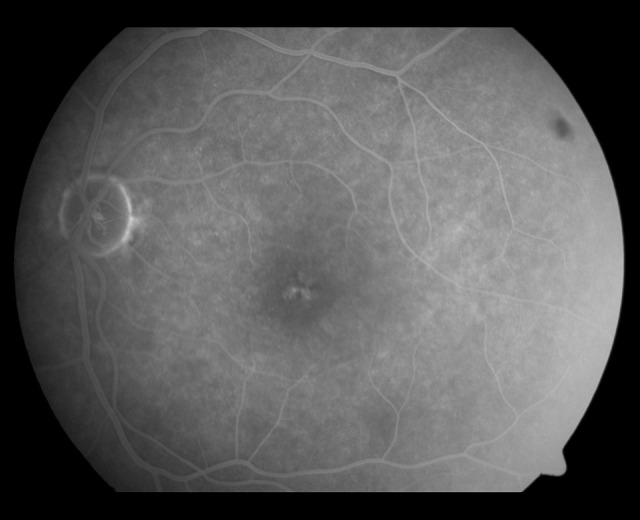

On examination of the left eye, visual acuity was 0.5 LogMAR, fundoscopy showed foveal pigment mobilization, fluoresce-in angiography revealed a hypofluorescent fovea surrounded by irregular hyperfluorescent defects (Figure 1), and SD-OCT showed central foveal thinning with disrupted interdigitation and ellipsoid zones (Figure 2). Other findings from the examination of the left eye were unremarkable.

Figure 1.

Fluorescein angiography of the left eye showed a hypofluorescent fovea surrounded by irregular hyperfluorescent defects, suggestive of acute macular neuroretinopathy.